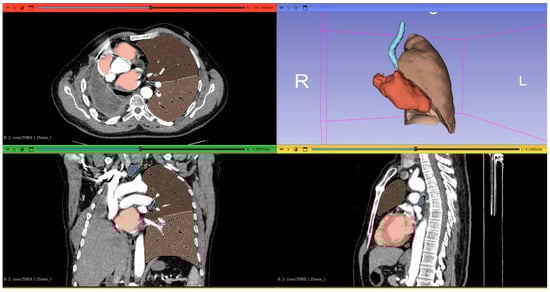

1. Introduction

2.2. Computed Tomography Image Acquisition and Postprocessing